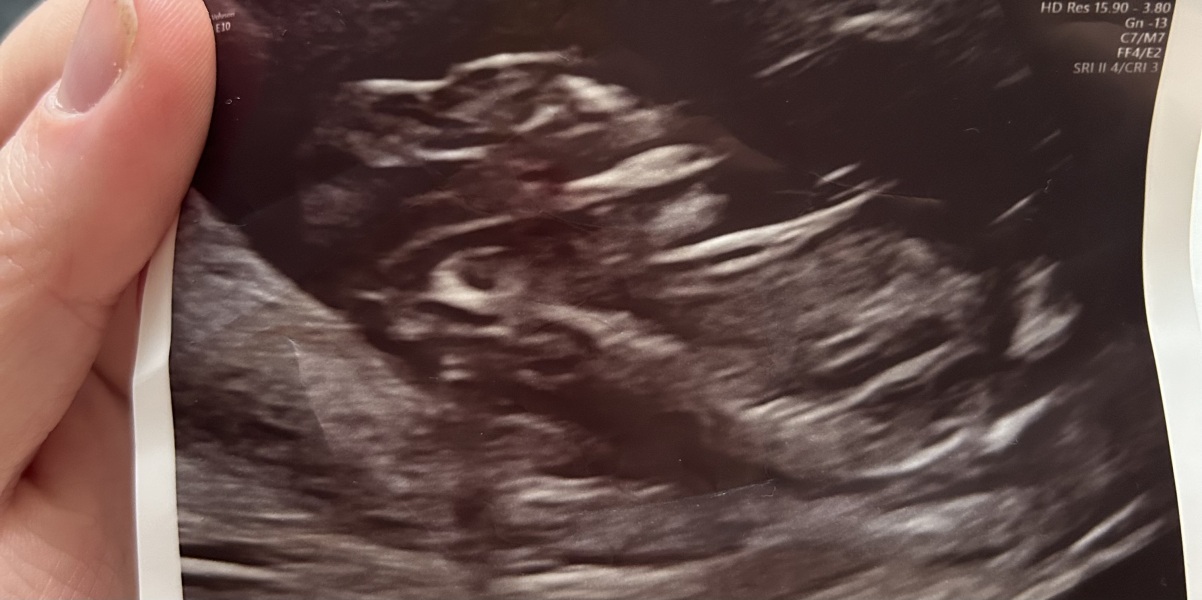

We’ve just come back from our nhs 12 week scan, I’m roughly 13weeks and 4 days (the sonographers didn’t actually give me a due date). Firstly, they were having a really tough time seeing anything. They couldn’t see my uterine vessels, took them ages to find my ovaries, and baby was completely vertical so they had much trouble doing the head to rump measurement. Worryingly, they have told me its head looks abnormal and are referring me to fetal medicine. The sonographer said “it could have dire consequences for your baby in the future.” Yet sometimes when they swiped over my belly, the head looked normal! I’m so confused and upset. I’ll attach a photo to show, but has anyone else been in this position and things turned out fine? ☹️ We’ve had private scans, one last week, and everything looked ok - nothing abnormal was mentioned. Oh they also said I didn’t need to have the blood tests to rule out downs/edward/patau syndrome yet. Which I’m worried about too because I’m nearly 14 weeks!